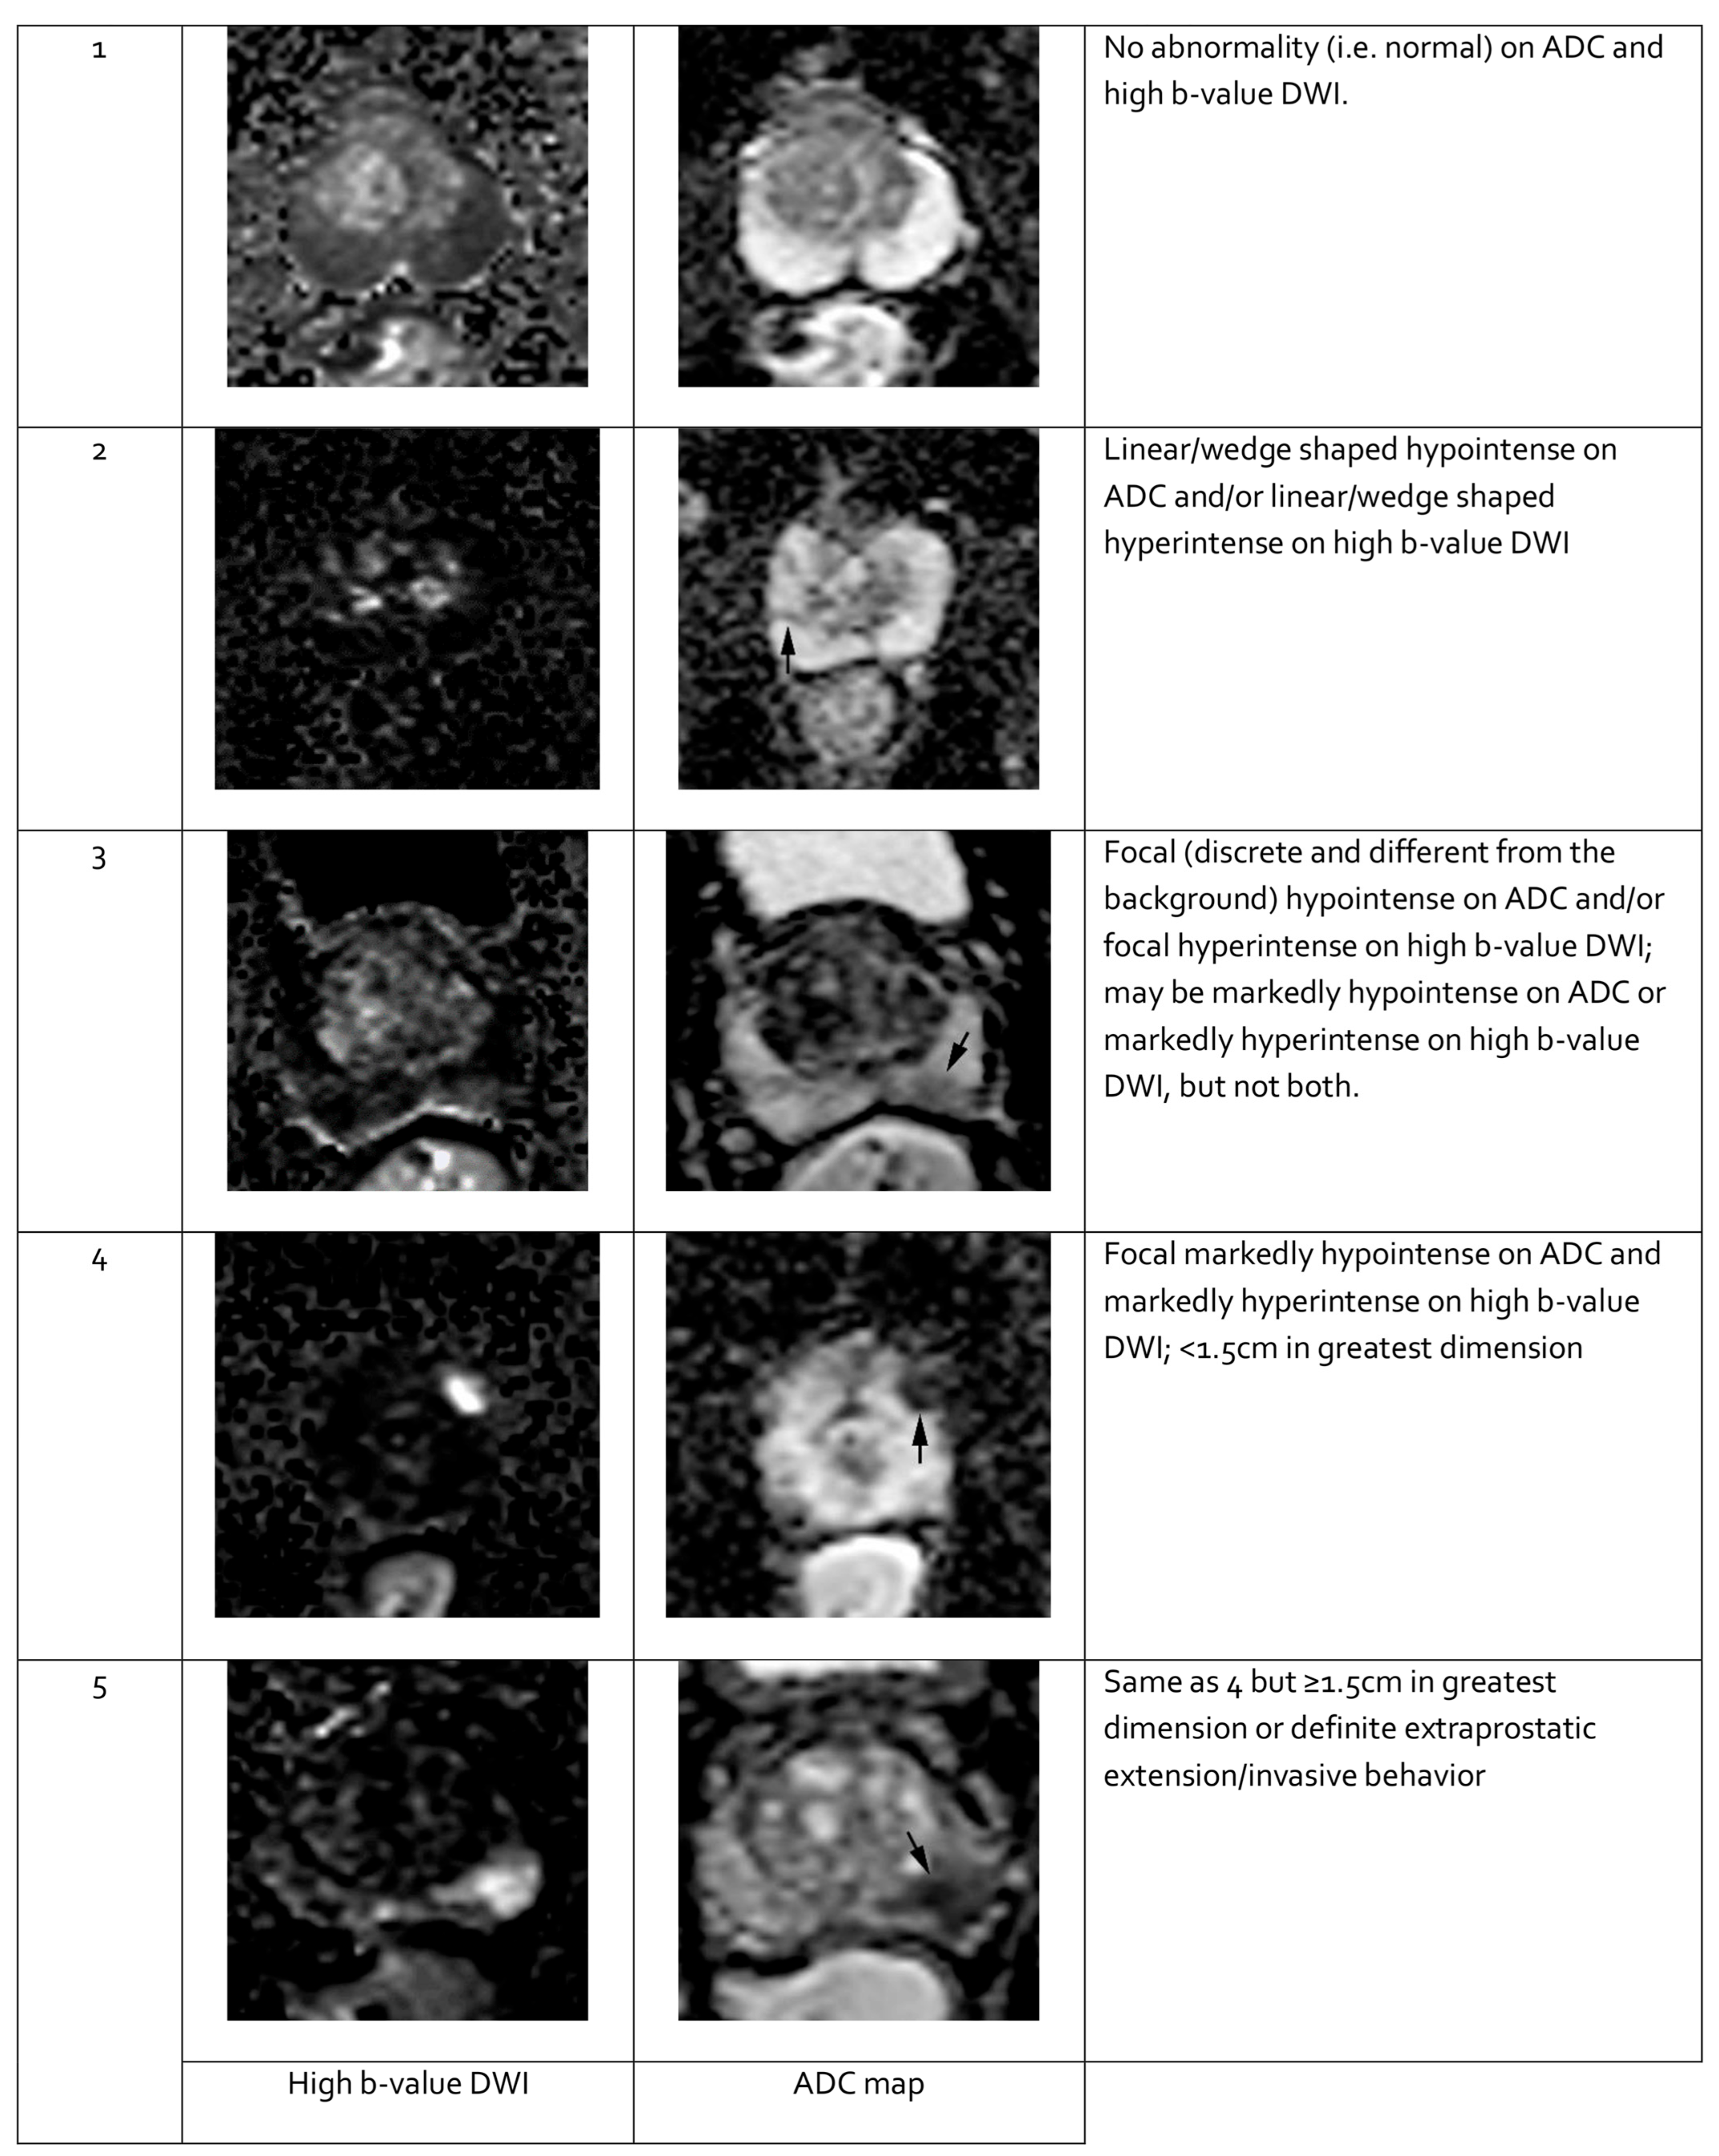

Features seen on mpMRI correlate with the likelihood of malignancy in visualized lesions. To standardize interpretation, the PI-RADS classification was developed. It assigns a score from 1 to 5 to mpMRI-detected lesions, reflecting their likelihood of malignancy [91] (see Table 3). The system is designed to ensure consistent lesion characterization, enhance targeted biopsy precision, and inform treatment decisions. In PI-RADS, each mpMRI sequence is evaluated separately as part of the overall assessment. The overall PI-RADS score is based on the dominant sequence in the affected prostate zone. The final PI-RADS assessment corresponds to the dominant lesion (index lesion) with the highest score within the evaluated prostate zone.

Table 3.

Risk of clinically significant prostate cancer (PCa) according to the Prostate Imaging—Reporting and Data System (PI-RADS) assessment categories based on multiparametric magnetic resonance imaging (mpMRI) findings [91]. Own work based on PI-RADS v2.1 [91].

PI-RADS classification should rely exclusively on mpMRI findings, without reference to PSA levels, DRE results, clinical history, or previous treatments. The detection rates of PCa with ISUP grade ≥ 2 based on PI-RADS scores are as follows: 9% (5–13%) for PI-RADS 1–2, 16% (7–27%) for PI-RADS 3, 59% (39–78%) for PI-RADS 4, and 85% (73–94%) for PI-RADS 5 [94].

When evaluating a lesion detected by mpMRI, its anatomical location is critical. T2-weighted images are most informative for lesions in the transition zone, while DWI is dominant for assessing the peripheral zone. Lesion measurements should be performed using the most informative imaging sequence for the specific prostate zone. Representative mpMRI images corresponding to PI-RADS scores are shown in Figure 3 and Figure 4. mpMRI is more effective in detecting clinically significant PCa lesions in the peripheral zone than in the transition zone. Given the growing number of mpMRI examinations, there is a trend toward simplifying protocols by omitting DCE. DCE plays a relatively minor role in primary PCa diagnosis and is associated with potential side effects, longer procedure time, and higher cost [95]. The role of DCE is more significant in the evaluation of local recurrences of cancer after radical treatment [96].

Figure 3.

Representative images of peripheral zone lesions of the prostate gland with various Prostate Imaging—Reporting and Data System (PI-RADS) scores. Reprinted from PI-RADS v2.1 [91] under a Creative Commons Attribution-NoDerivatives (CC BY-ND) 4.0 International License available at https://creativecommons.org/licenses/by-nd/4.0/. ADC: apparent diffusion coefficient; DWI: diffusion-weighted imaging. Black arrows indicate lesions in the respective PI-RADS scores.